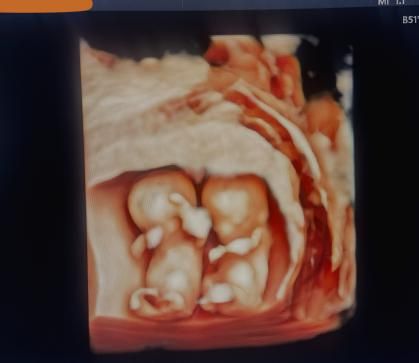

近期一位孕19周+的双胎孕妇,早孕期NT检查提示双绒毛膜双羊膜囊,测得NT值均增厚:A胎3.3mm、B胎3.6mm,产科医生告知相关染色体异常的风险及产前诊断的局限性后,孕妇及家属接受了双胎羊水穿刺术。超声科瓦迎芳主任医师与产科刘健男主任医师通过丰富临床经验,密切配合,使用6LP3型号专用穿刺探头进行精准定位,选取最短安全穿刺路径,由于A胎胎盘位于子宫前壁,B胎位于后壁,故先进行了B胎穿刺,后进行了A胎穿刺,仅用10分钟顺利完成我院第一例双胎产前诊断取样,术后孕妇无不适。标志我院产前诊断技术新技术迈上新台阶。